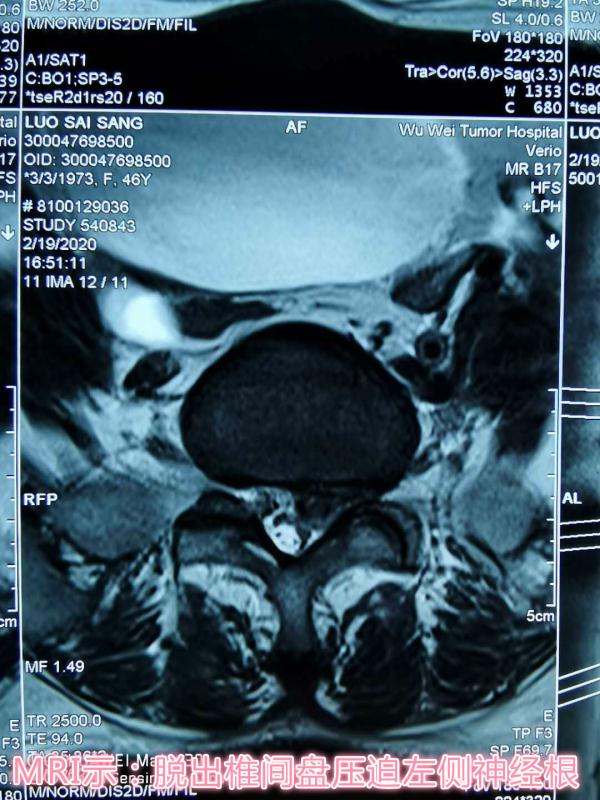

患者,女性,47岁,左下肢疼痛伴麻木1年,加重两月。入院后,骨科医护团队立即完善相关检查,仔细察看患者病情发展情况,为其制定了精准的治疗方案,同时向患者及家属详细讲解了手术的优势及术后的注意事项,患者及家属表示理解并同意手术。术中一切顺利,术后患者次日即可下地活动,大大缩短了传统Tlif术后需卧床三月的修复时间。